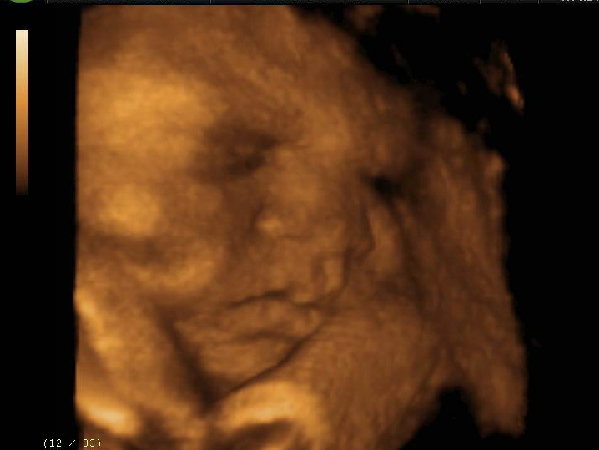

Múlt héten pénteken elmentünk egy másik helyre 4d-t csináltatni és most végre van egy nagyon helyes képem, igaz, fél profil, de nekem nagyon bejön. Tiszta apja :D

Vica, ez nagyon jó kép! majd ha megszületik a kisfiad, hasonlítsátok össze! utolsó hónap :D ez nagyon izgi :D és a nevét kitaláltátok már, ugye?

Vica :) Kép szuper a pocaklakódról :D :D Hű, már az utolsó hónap! :) Fütyüléshez még annyit, hogy múltkor anyós után fütyültek, amikor hazafelé bicajozott baseball sapóban és napszemüvegben, majd amikor mellé értek volt meglepetés...

Megtaláltam párom csecsemő kori képét és azzal is összevetettem - meg majd születése után is -, és tényleg tiszta apja. :)

kisfiad portréja nagyon jó! :)

A tuti favorittal kapcsolatban még csak a magam nevében beszélhetek. Szóval: Ádám Máté, vagy Máté Ádám. Jajj, most remélem nem kapok majd a páromtól :D

Nagyon édes a kép a piciről :D Nekünk teljesen profilból sikerült annak idején, és utólag megállapítottuk, hogy nagyon hasonlít Bazsó a képre.